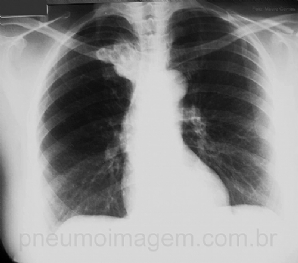

CASO CLÍNICO #8

Paciente jovem, apresenta-se com tosse, febre alta (39 C) e dor torácica com início há 2 dias. Alguns raros EC na base pulmonar direita. Olhe atentamente essa radiografia de tórax e diga qual seria a sua conduta. Você trataria como pneumonia? Deixe seu comentá...